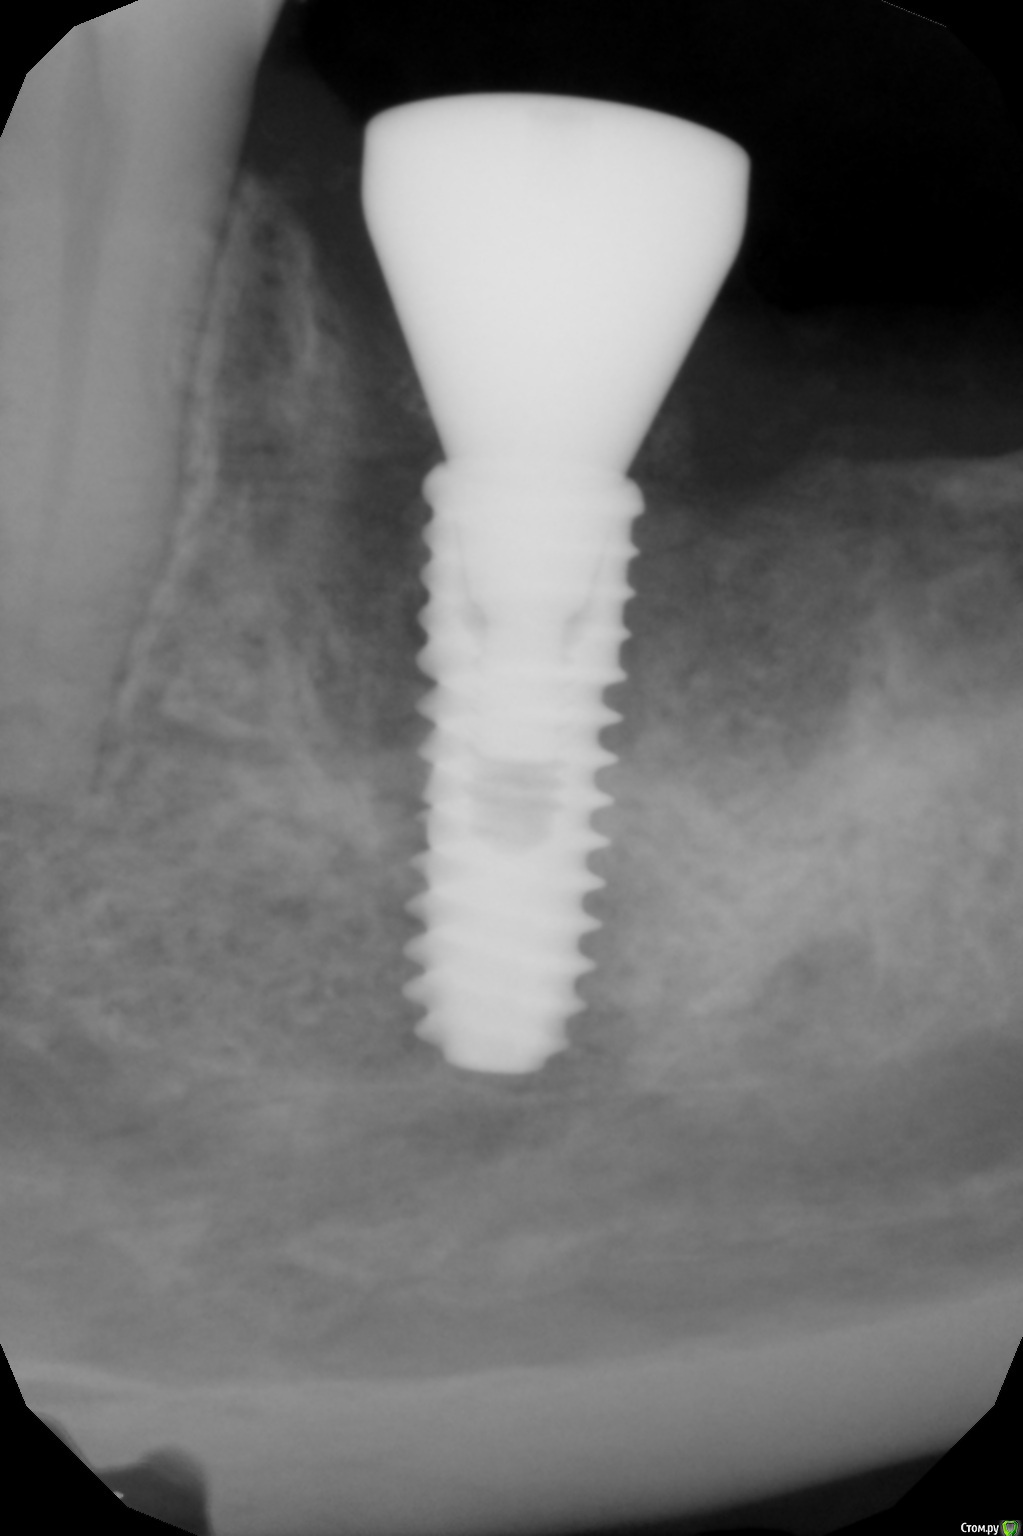

kamranchick Опубликовано 4 февраля, 2017 Поделиться Опубликовано 4 февраля, 2017 (изменено) чтобы не создавать новую тему...Ваши мысли коллеги? между снимками 2 месяца Изменено 4 февраля, 2017 пользователем kamranchick Ссылка на комментарий

Большой Зеленый Опубликовано 4 февраля, 2017 Поделиться Опубликовано 4 февраля, 2017 чтобы не создавать новую тему...Ваши мысли коллеги? между снимками 2 месяцаОткрутить формик и под заглушку.Давление формирователя на кость спровоцировало периимплантит Ссылка на комментарий

kamranchick Опубликовано 4 февраля, 2017 Поделиться Опубликовано 4 февраля, 2017 Открутить формик и под заглушку.Давление формирователя на кость спровоцировало периимплантитА зачем под заглушку? Сейчас вроде нет давления формирователя Ссылка на комментарий

dzhancha Опубликовано 25 января, 2018 Поделиться Опубликовано 25 января, 2018 Открутить формик и под заглушку.Давление формирователя на кость спровоцировало периимплантитЦелесообразнее использовать узкие формирователи при такой установке? Ссылка на комментарий

Большой Зеленый Опубликовано 26 января, 2018 Поделиться Опубликовано 26 января, 2018 Целесообразнее использовать узкие формирователи при такой установке?Однозначно. Есть специальные фрезы которые позволяют поставить формирователь без давления на кость. Нобелевские видео про "Все на четырех" посмотрите. Ссылка на комментарий